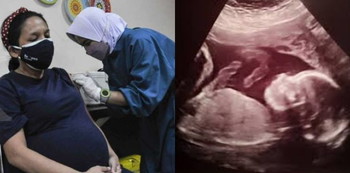

Bukan sahaja vaksin selamat untuk ibu mengandung, malah antibodi yang dihasilkan bila ibu memperoleh vaksin sewaktu mengandung akan diturunkan pada bayi yang belum dilahirkan, jadi bayi anda juga memperoleh perlindungan bagi menentang Covid apabila dia dilahirkan.

Vaksin booster Covid ini adalah SANGAT SELAMAT diambil pada bila-bila masa kehamilan. Ia bukan sahaja melindungi ibu, malah melindungi bayi juga. Justeru jangan tangguhkan dan tidak perlu menunggu selepas beranak.